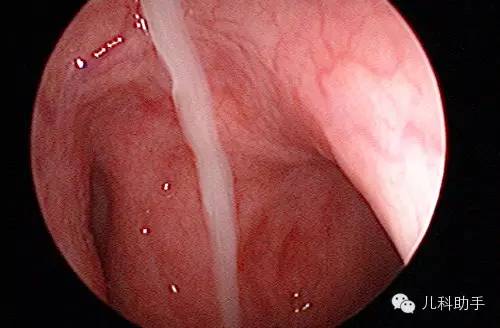

4.体征变应性鼻炎的鼻黏膜主要表现为苍白或水肿,鼻道及鼻腔底可见清涕或黏涕。非变应性鼻炎鼻黏膜多表现为黏膜肥厚或充血样改变,部分患者口咽部黏膜可呈鹅卵石样改变,黏膜充血、水肿,咽后壁附有黏性分泌物。肺部可无任何阳性体征。

由于鼻窦炎经常继发于鼻炎,很少有不伴鼻炎的情况,因此目前多用“鼻-鼻窦炎”这一概念取代“鼻窦炎”。2012年中华医学会耳鼻喉科头颈外科分会制定了《慢性鼻-鼻窦炎诊断和治疗指南》。指南将慢性鼻-鼻窦炎定义为鼻窦与鼻腔黏膜的慢性炎症,病程超过12周。诊断主要依据为临床症状,结合鼻腔检查所见和鼻窦放射影像学检查(CT)所见。临床症状包括主要症状(鼻塞,黏性、脓性鼻涕)和次要症状(头面部胀痛,嗅觉减退或丧失),诊断时要具备两种或两种以上相关症状,其中主要症状必含其一。鼻腔检查可见来源于中鼻道、嗅裂的黏脓性分泌物,中鼻道黏膜充血、水肿或有鼻息肉。鼻窦CT检查显示窦口鼻道复合体和(或)鼻道黏膜炎性病变。